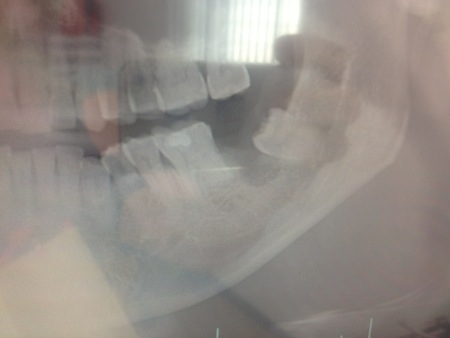

よく見ると歯の横の部分が削れているのがわかるだろう。

ちなみにこれは歯が抜けてしまった後のレントゲン!!

この親知らずの尖った部分がこの歯の凹んだ部分に食い込んでいたということやな。